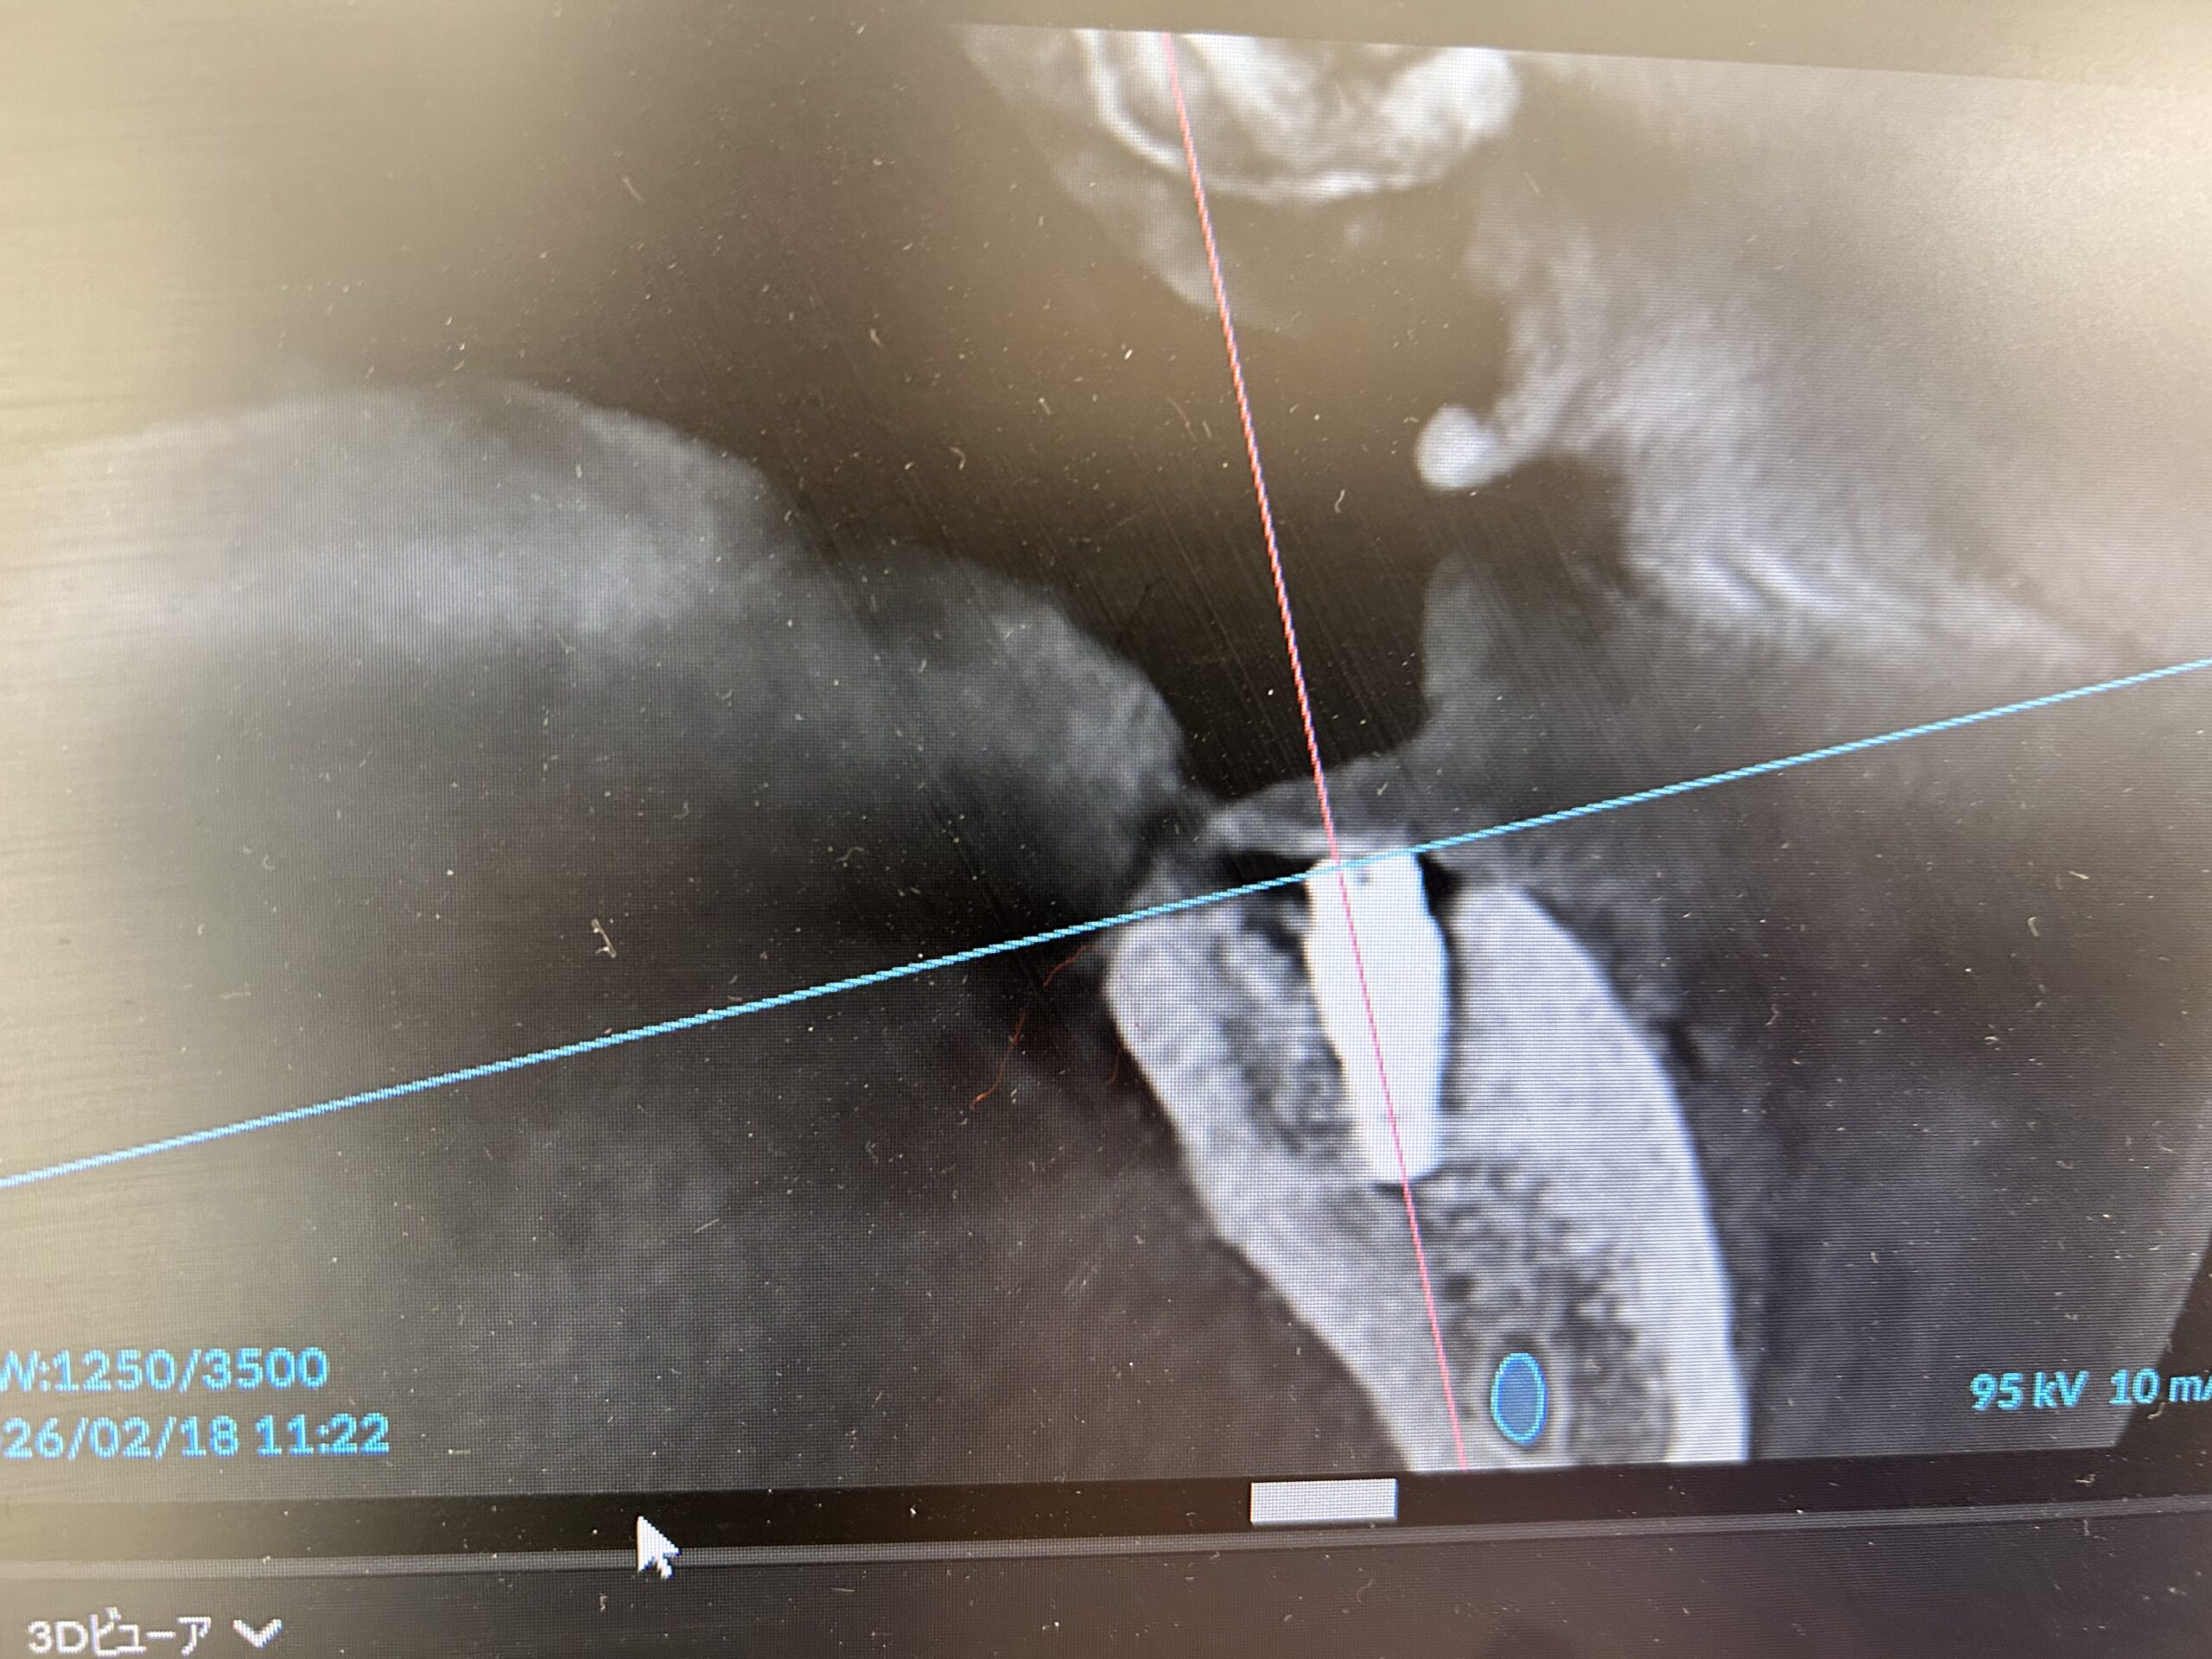

遂に今日(2/18)、インプラントの土台を埋め込んできました。

チタンの土台を埋め込んだ後、歯茎を10針縫って約50分で手術終了です。